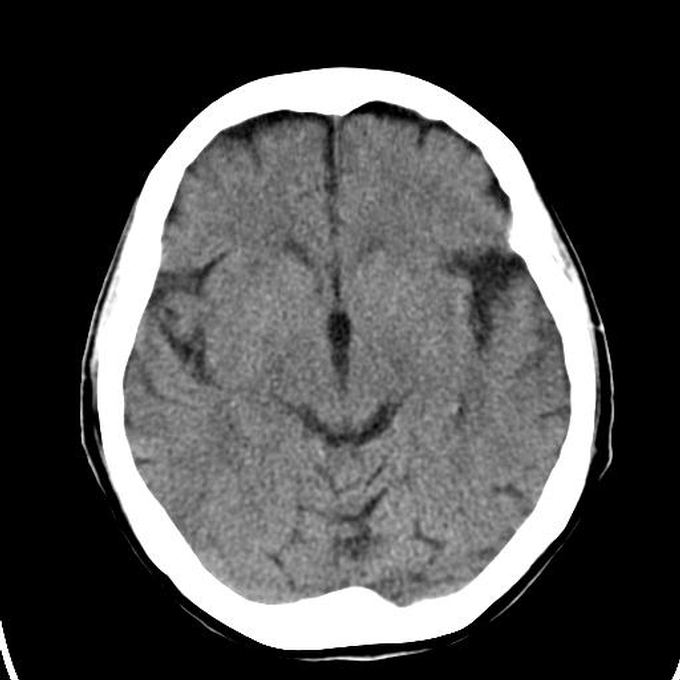

56 year old patient with dyspagia. A tumor of soft tissue was described in upper mediastinum on plain X-ray of the thorax. What is this mass in the upper mediastinum?